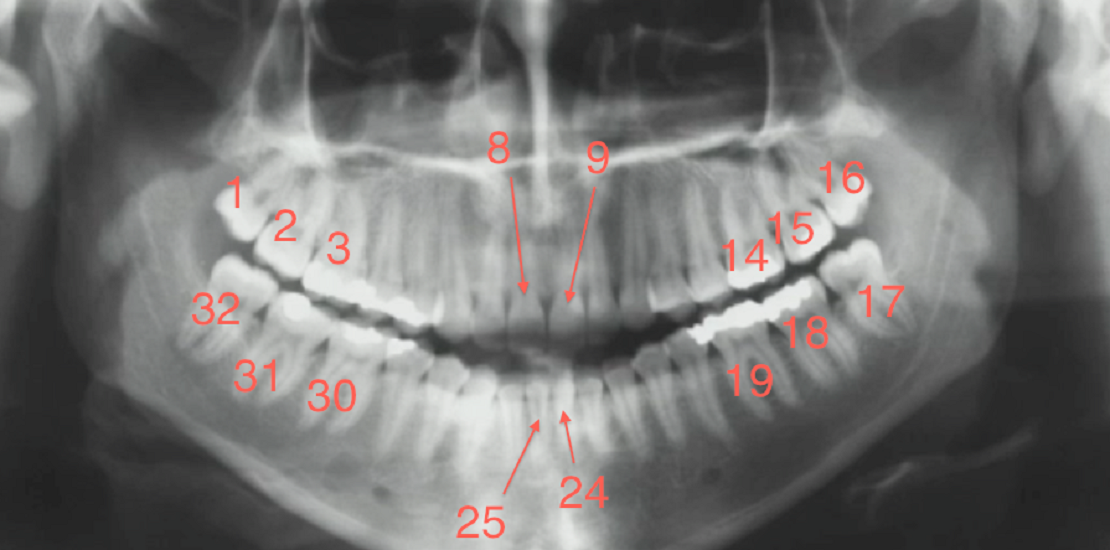

روش یونیورسال (Universal Numbering System) رایجترین روش برای نامگذاری دندان ها در کشور آمریکا است. در این روش به دندان های دائمی عددی از 1 تا 32 و به دندان های شیری کودکان عددی از 1 تا 20 داده میشود. شماره گذاری نیز از کوادران 1 (از سمت راست فک بالا و از دندان عقل یا دندان آسیای سوم) آغاز میشود و آخرین دندانی که شماره 32 میگیرد، دندانِ عقلِ فکِ پایین در سمت راست است.

در سیستم شماره گذاری جهانی، دندانهای عقل با شمارههای 1، 16، 17 و 32 شماره گذاری میشوند. آنها آخرین دندانها در هر ربع هستند که به عنوان دندان آسیاب سوم تعیین میشوند.

دندانهای جلو یا دندانهای ثنایا و نیش در بزرگسالان 6-11 (جلو بالا) و 22-27 (جلو پایین) شماره گذاری میشوند. دندانهای آسیاب یا دندانهای عقب معمولاً شامل اعداد 1-3، 14-16، 17-19 و 30-32 میشوند.

در فک بالا، دندانها از دندان مولر راست (دندان شماره 1) تا دندان آسیاب چپ (دندان شماره 16) شماره گذاری میشوند. در شماره دندان ها فک پایین، شماره گذاری از مولر چپ (دندان شماره 17) شروع میشود و به سمت آسیاب راست (دندان شماره 32) میرود.

شمارش دندان معمولاً با استفاده از نمودار شماره دندان ها و با یک سیستم شماره گذاری جهانی و استاندارد انجام میشود. در سیستم جهانی، دندان ها از 1 تا 32 شماره گذاری می شوند که از دندان آسیاب سوم بالا سمت راست شروع می شود، به سمت چپ به سمت مولر سوم بالا سمت چپ حرکت می کند، سپس به سمت آسیاب سوم پایین سمت چپ حرکت میکند و به مولر سوم سمت راست پایین ختم می شوند.